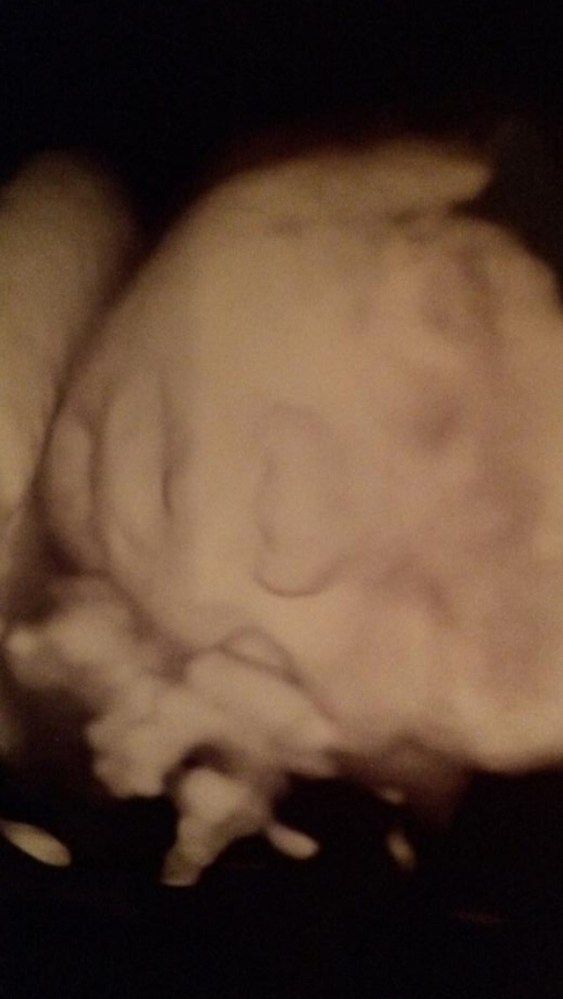

The ultrasound report also confirmed what we already knew; all other areas of his body are growing and developing normally, with the exception of the left side of his heart. His specific conditions are known as critical aortic stenosis and borderline left heart syndrome, and these are causing a number of other problems. The procedure, when successful, will stretch the aortic valve to release some of the pressure, allow blood to flow through the aorta and rest of the heart as it was designed, provide the next couple of months for his heart to heal from some of the damage, and allow it to continue to develop. We are praying for a successful procedure, the opportunity to carry him to full term, and for Kaden’s heart to heal.

Next, we met with the cardiologists, including Dr. Tworetzky. They completed another fetal echocardiogram and reviewed all of our previous records. The 18-week ultrasound was unremarkable; there was nothing missed. His condition (critical aortic stenosis) is fast-progressing and we are grateful to have found this when we did. Ultimately, the purpose of the procedure is to prevent Hypoplastic Left Heart Syndrome (HLHS). For most children, this is a condition that requires multiple surgeries and a limited life span. Based on the last week’s chain of events, we are confident in how we were led here and moving forward with the procedure. There are absolute risks in doing the fetal intervention, yet we feel the risks of doing nothing at all are much greater. We understand there is some controversy per Dr. Google; however we have chose to listen to our Maker, and then the pros.